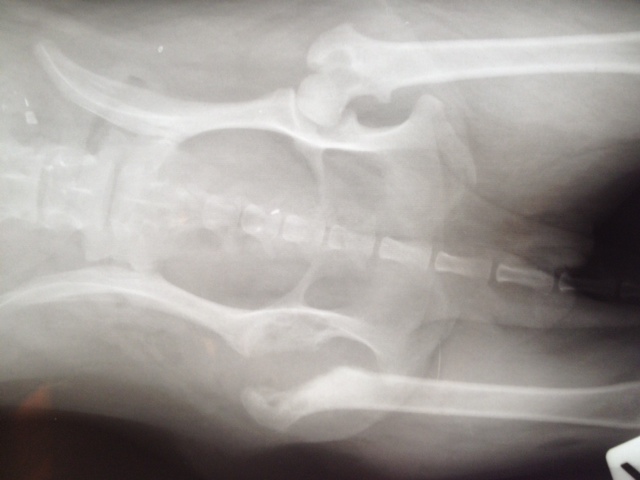

Aber Felipa ließ das eine Hinterbeinchen neuerdings so eigenartig hängen und trat nicht mehr damit auf. Also ließen wir es abklären. Es stellte sich heraus, dass sich der Knorpel des Oberschenkelhalskopfes zersetzt.

Die Ursache dafür sind genetisch bedingte Durchblutungsstörungen. Das kommt bei einigen kleineren Rassen vor. Es hat nichts mit der OP am Vorderbein zu tun.

Also hatte Felipa heute (01.08.) ihre 2.OP - allerdings wie gesagt ganz anders als geplant. Der Chirurg entfernte den kaputten Knorpel, wie man auch als Laie an den Aufnahmen gut erkennen kann.